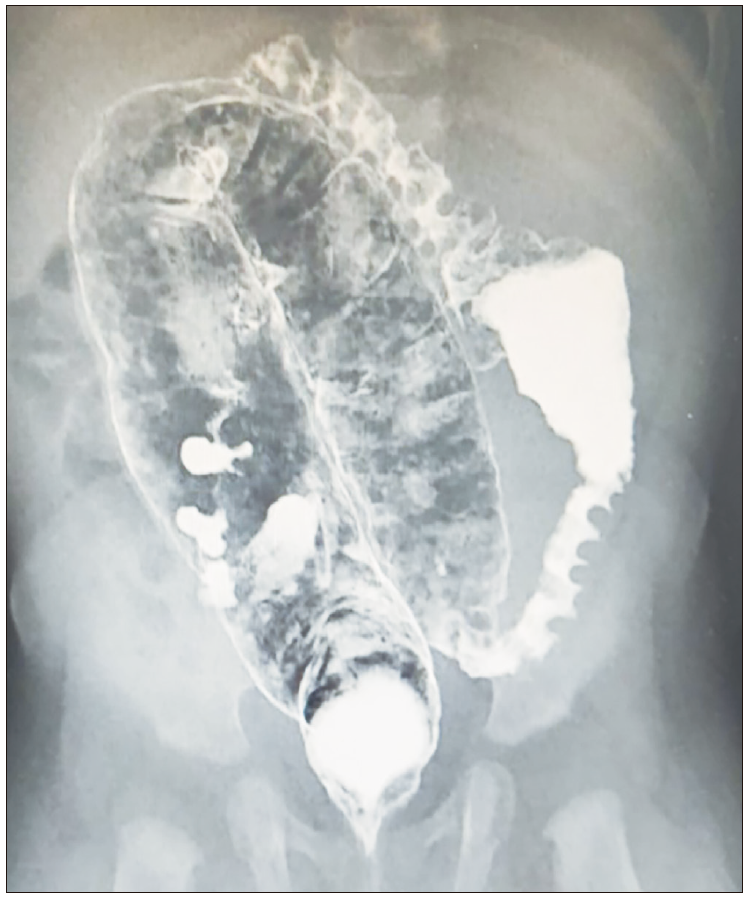

La paciente recibía lactancia materna exclusiva, por lo cual inicialmente se indicó continuarla, con dieta de exclusión de leche de vaca. Sin embargo, a los tres días de iniciada, empeora el cuadro clínico, con presencia de múltiples episodios eméticos e intolerancia a la vía oral. Se ampliaron los estudios, entre ellos una radiografía de abdomen, con imagen sugestiva de vólvulo intestinal. Se solicita una radiografía de colon por enema, en la que se observa una marcada distensión del colon sigmoides, con un índice rectosigmoideo menor a 1, hallazgo que podría relacionarse con EH (Figura 1). Posteriormente, se realiza una biopsia endorrectal, que reporta la presencia de células ganglionares e inervación morfológicamente usual.

Figura 1. Enema con bario con marcada distensión del colon sigmoide con índice

rectosigmoideo menor a 1

En relación con la fisiopatología, en la APLV existen diferentes rutas inmunológicas. Existe una respuesta inflamatoria dentro del colon rectosigmoide e infiltración principalmente de eosinófilos, los cuales son activados a través de citoquinas (IL-4, IL-5, IL-13 y TNF) por parte de linfocitos TH2 y células plasmáticas, promoviendo la producción de IgE y la degranulación de los eosinófilos, con la liberación de proteínas con efectos proinflamatorios,14 siendo estos considerados como factores predisponentes para que se presente dismotilidad colónica y estrechamiento espástico del recto inducido por el cambio inflamatorio inmunológico.4 Aunque hay pocas publicaciones en relación con los hallazgos radiológicos de la colitis alérgica, usualmente se ha evidenciado edema de la mucosa y estrechamiento de la luz colónica por engrosamiento de los pliegues del intestino delgado en el enema de bario similar a la EH.4,13

Con relación al caso clínico, se observa que la paciente presentaba síntomas gastrointestinales y hallazgos al examen físico, con xerodermia generalizada, deposiciones con moco y eritema perianal, que hacían sospechar APLV, por lo cual se indicó dieta de exclusión de leche de vaca. A los tres días de iniciada la dieta, empeora el cuadro, por lo cual se amplían los estudios por imágenes, que mostraron una marcada distensión del colon sigmoides, que podría relacionarse con EH. Sin embargo, los hallazgos de la biopsia endorrectal descartaron EH, confirmando el diagnóstico de APLV tras iniciar fórmula a base de aminoácidos y observando la mejoría clínica presentada por la paciente.